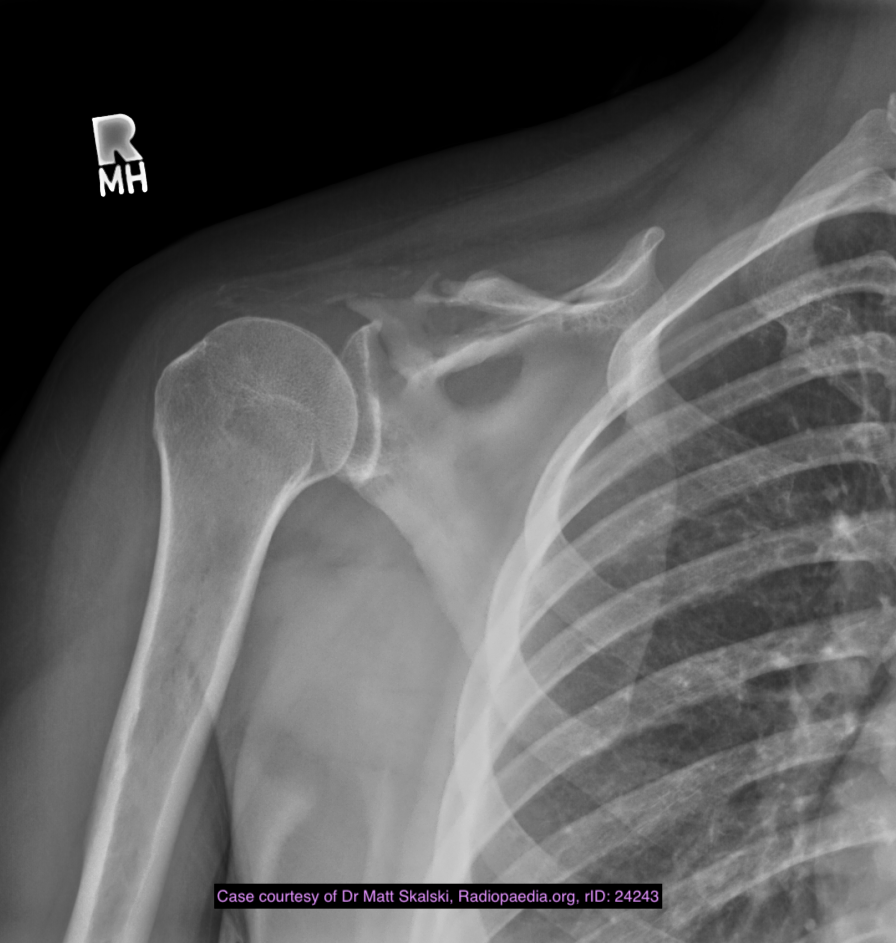

Gorham disease or vanishing bone disease is a poorly understood rare skeletal condition which manifests with massive progressive osteolysis along with a proliferation of thin walled vascular channels. The disease starts in one bone but may spread to involve adjacent bony and soft tissue structures.

Signs and symptoms are incredibly varied depending on the bones involved, and may only become apparent after a fracture.

The osteolysis is thought to be due to an increased number of stimulated osteoclasts 3, which is likely secondary to abundant non-neoplastic vascular and lymphatic proliferation in the affected region 9. The bone is subsequently replaced by variable amounts of fibrous connective tissue that is hypervascular10.

Location

Gorham disease can potentially involve any bone. Reported sites include:

humerus (first reported case)

shoulder girdle

Plain radiograph and CT

intramedullary or subcortical lucent foci may be the earliest manifestation 1

this progresses to profound osteolysis with resorption of affected bone and lack of compensatory osteoblastic activity or periosteal reaction

Differential diagnosis

Imaging differential considerations include:

generalised lymphatic anomaly

multifocal lymphatic malformations, including intramedullary bone lesions

does not classically cause progressive osteolysis 11

osteolytic metastases

osteolytic primary bone lesion

multiple myeloma

osteomyelitis

rapidly progressive osteoarthritis

Milwaukee shoulder

multicentric carpal tarsal osteolysis